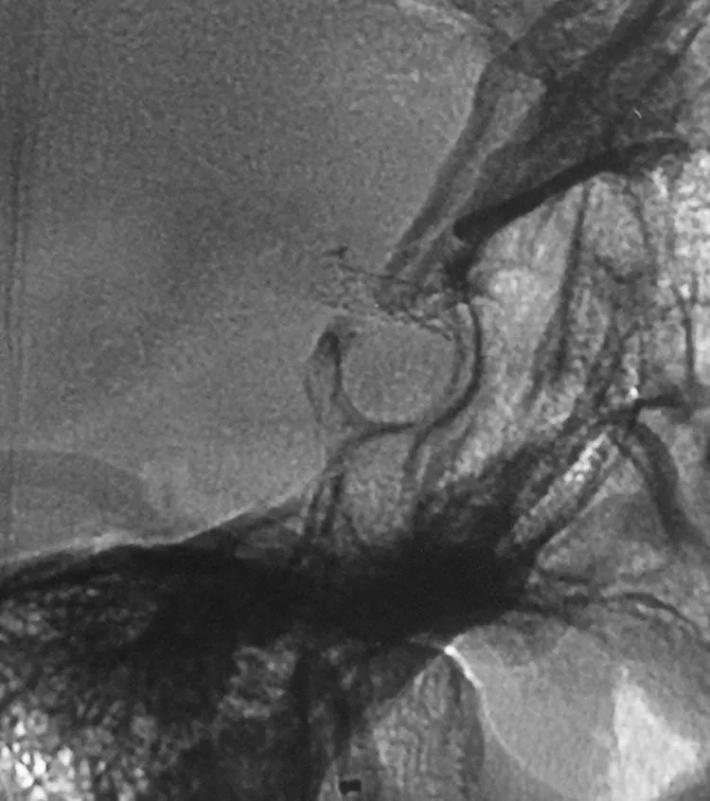

R-ICA正位:颈内动脉床突上段局部膨隆

R-ICA斜位:可见床突上段前壁一蘑菇状囊性突起,结合cT出血提示BBA,与家属沟通后选择介入治疗,我们拟采用Willis覆膜支架局部血管成形术!